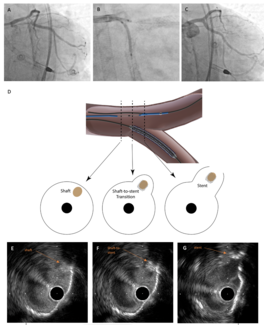

Ho Figure 1

Video Supplement to "Real-Time IVUS-Guided Minimal CRUSH for Bifurcation Stenting: The IM-CRUSH Technique" (Clinical Image).

04/15/2025

Cheuk Bong Ho, MBBS; Calvin Leung, MBChB; Michael Chi Shing Chiang, MBBS; Esmond Yan Hang Fong, MBBS; Shing Fung Chui, MBBS; Ka Chun Chan, MBBS; Chi Yuen Wong, MBBS; Michael Kang Yin Lee, MBBS

A 72-year-old woman with diabetic nephropathy was admitted for non-ST segment elevation myocardial infarction. She had undergone percutaneous coronary intervention to the ostial left anterior descending and left circumflex arteries 2 years...